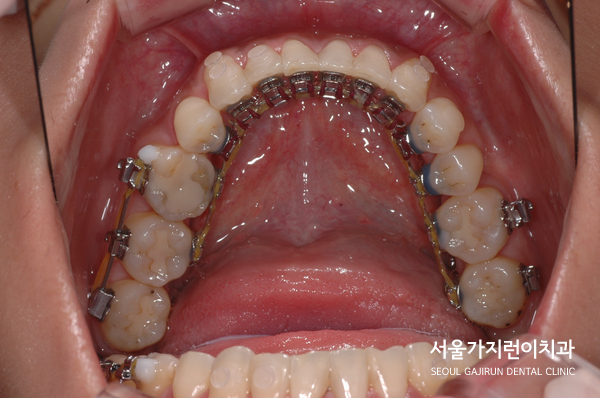

그래서 본원에서는 환자의 상태를 확인한 후에 사랑니를 어금니도 대체하는 치아교정을 진행했었는데요. 환자분께는 레버암과 미니스크류를 동시에 사용해 어금니가 쓰러지지 않고 전방으로 이동하면서 사랑니를 끌어다 사용할 수 있도록 치아교정 계획을 수립했었습니다.

결국 환자분이 원하는 것처럼 설측교정방식을 이용한 치아교정을 진행했으며 공간의 폐쇄와 더불어 사랑니를 세워 어금니로 활용할 수 있게 만들었는데요. 교정을 마친 후를 보면 정상교합으로 달성된 것을 확인할 수 있으며 발치로 인한 공간을 잘 폐쇄하였습니다. 여기에 주걱턱 느낌도 교정을 마쳤는데요. 모든 케이스에 적용가능한 것은 아니지만 상기 환자와 비슷한 사랑니 치아교정이 고민된다면 교정전문치과 서울가지런이치과 교정과 의원을 방문해보시기 바랍니다.